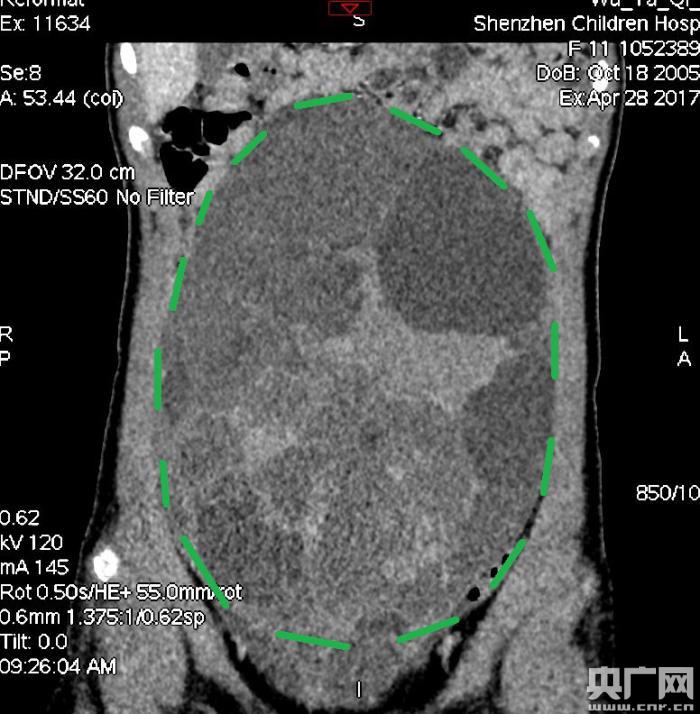

入院后,普外一科肖東主任向家長(zhǎng)詢問(wèn)了病史,仔細(xì)進(jìn)行了體格檢查,并完善腹部CT。CT結(jié)果提示,孩子的大部分腹腔、盆腔被一個(gè)巨大的腫瘤占據(jù),腸道、血管和腎盂都受到了不同程度的壓迫。從CT上看,腫瘤很可能起源于左側(cè)的卵巢。

手術(shù)中發(fā)現(xiàn),小琪腹中的腫瘤體積巨大,大小約為25×20×15厘米,表面光滑,來(lái)源于左側(cè)卵巢。醫(yī)生們首先將其與周?chē)慕M織小心剝離,然后將這個(gè)占據(jù)孩子腹腔、盆腔大部分的巨大包塊完整切除,切除腫瘤后還重建了左側(cè)卵巢。剖開(kāi)瘤體,發(fā)現(xiàn)瘤體為囊性及實(shí)性混合組成,瘤體內(nèi)部充盈著粘液狀的液體,重量達(dá)到了3000克。術(shù)后小琪病情穩(wěn)定,測(cè)量腹圍從術(shù)前的72厘米減小到了62厘米。